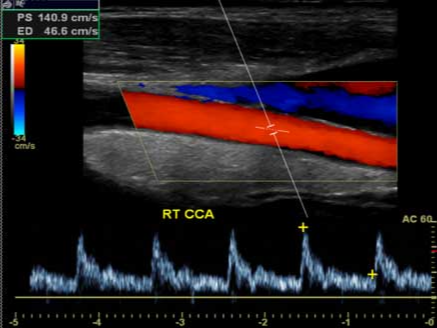

- 도플러 초음파: 혈류의 속도와 방향, 스펙트럼을 분석해 협착 정도를 정량화합니다.

죽상경화로 혈관 내강이 좁아지면 도플러에서 최고수축기속도(PSV) 상승, 난류, 스펙트럼 확산이 관찰됩니다. 중등도 이상의 협착은 뇌졸중 위험 상승과 연관되므로 항혈소판제, 스타틴 강화, 혈압·당뇨·지질 교정, 금연 등 집중적 위험인자 관리가 필요합니다. 특정 기준을 만족하는 중증 협착에서는 경동맥 내막절제술(CEA)이나 스텐트 삽입이 검토됩니다.

- PSV/EDV: 최고수축기속도/말기이완기속도. 협착이 심할수록 PSV 상승, EDV 변화 동반.

- ICA/CCA 속도비: 협착의 상대적 지표로 활용.